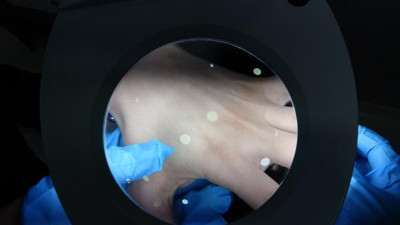

Uzmanından kritik uyarı. Bir kent diken üstünde Sakın ötelemeyin Trabzon'da kaşıntı ile ortaya çıkan ve alerji diye önemsenmediği için doktora gidilmemesi nedeniyle uyuz hastalığında ciddi artışlar yaşanmaya başladı. Uyuz hastalığı yurtta kalan öğrenciler arasında yaygın hale gelirken Dermatoloji Uzmanı Dr. Hikmet Akyazı, vatandaşları uyardı.